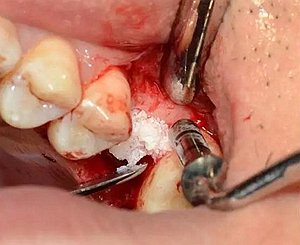

逐次添加少量骨粉,加壓到位,反復(fù)進行。骨粉總量約0.25g